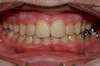

Fentes palatines bilatérales, cas traité au cabinet d'orthodontie du Dr Le petit à Bordeaux

Intra Orale Face